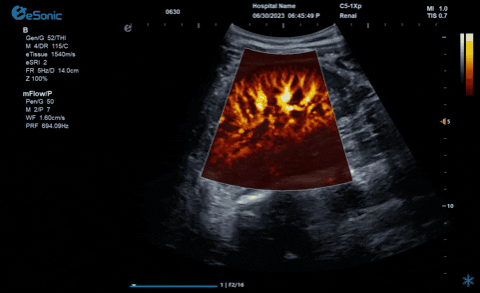

利来国国际网站医疗的eHertz系列彩色多谱超声诊断系统凭借强大的RawVision?原数精准平台和SDBeam?软波声束合成技术推出专属的mFlow ?超微血流显像技术,该项技术可专用于极低速血流成像。彩色多普勒血流(CDFI)检查时,通常会将滤波器的频率设置为大约50hz,并随时调整标尺和增益,以便在背景噪声发生前显示小血管......